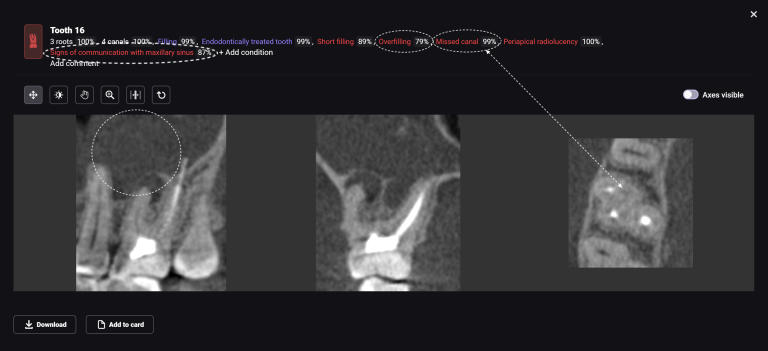

In this clinical case, the surgeon was tasked with correcting the pink aesthetics of the patient prior to the start of prosthetic treatment. Let’s explore how a clinician can leverage the capabilities of Diagnocat in such situations

Combining DICOM data and intraoral scans in Diagnocat STL module allows for the creation of 3D models